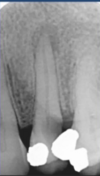

Q

what other radiographs other than periapicals can be used to assess periapical inflamm pathology?